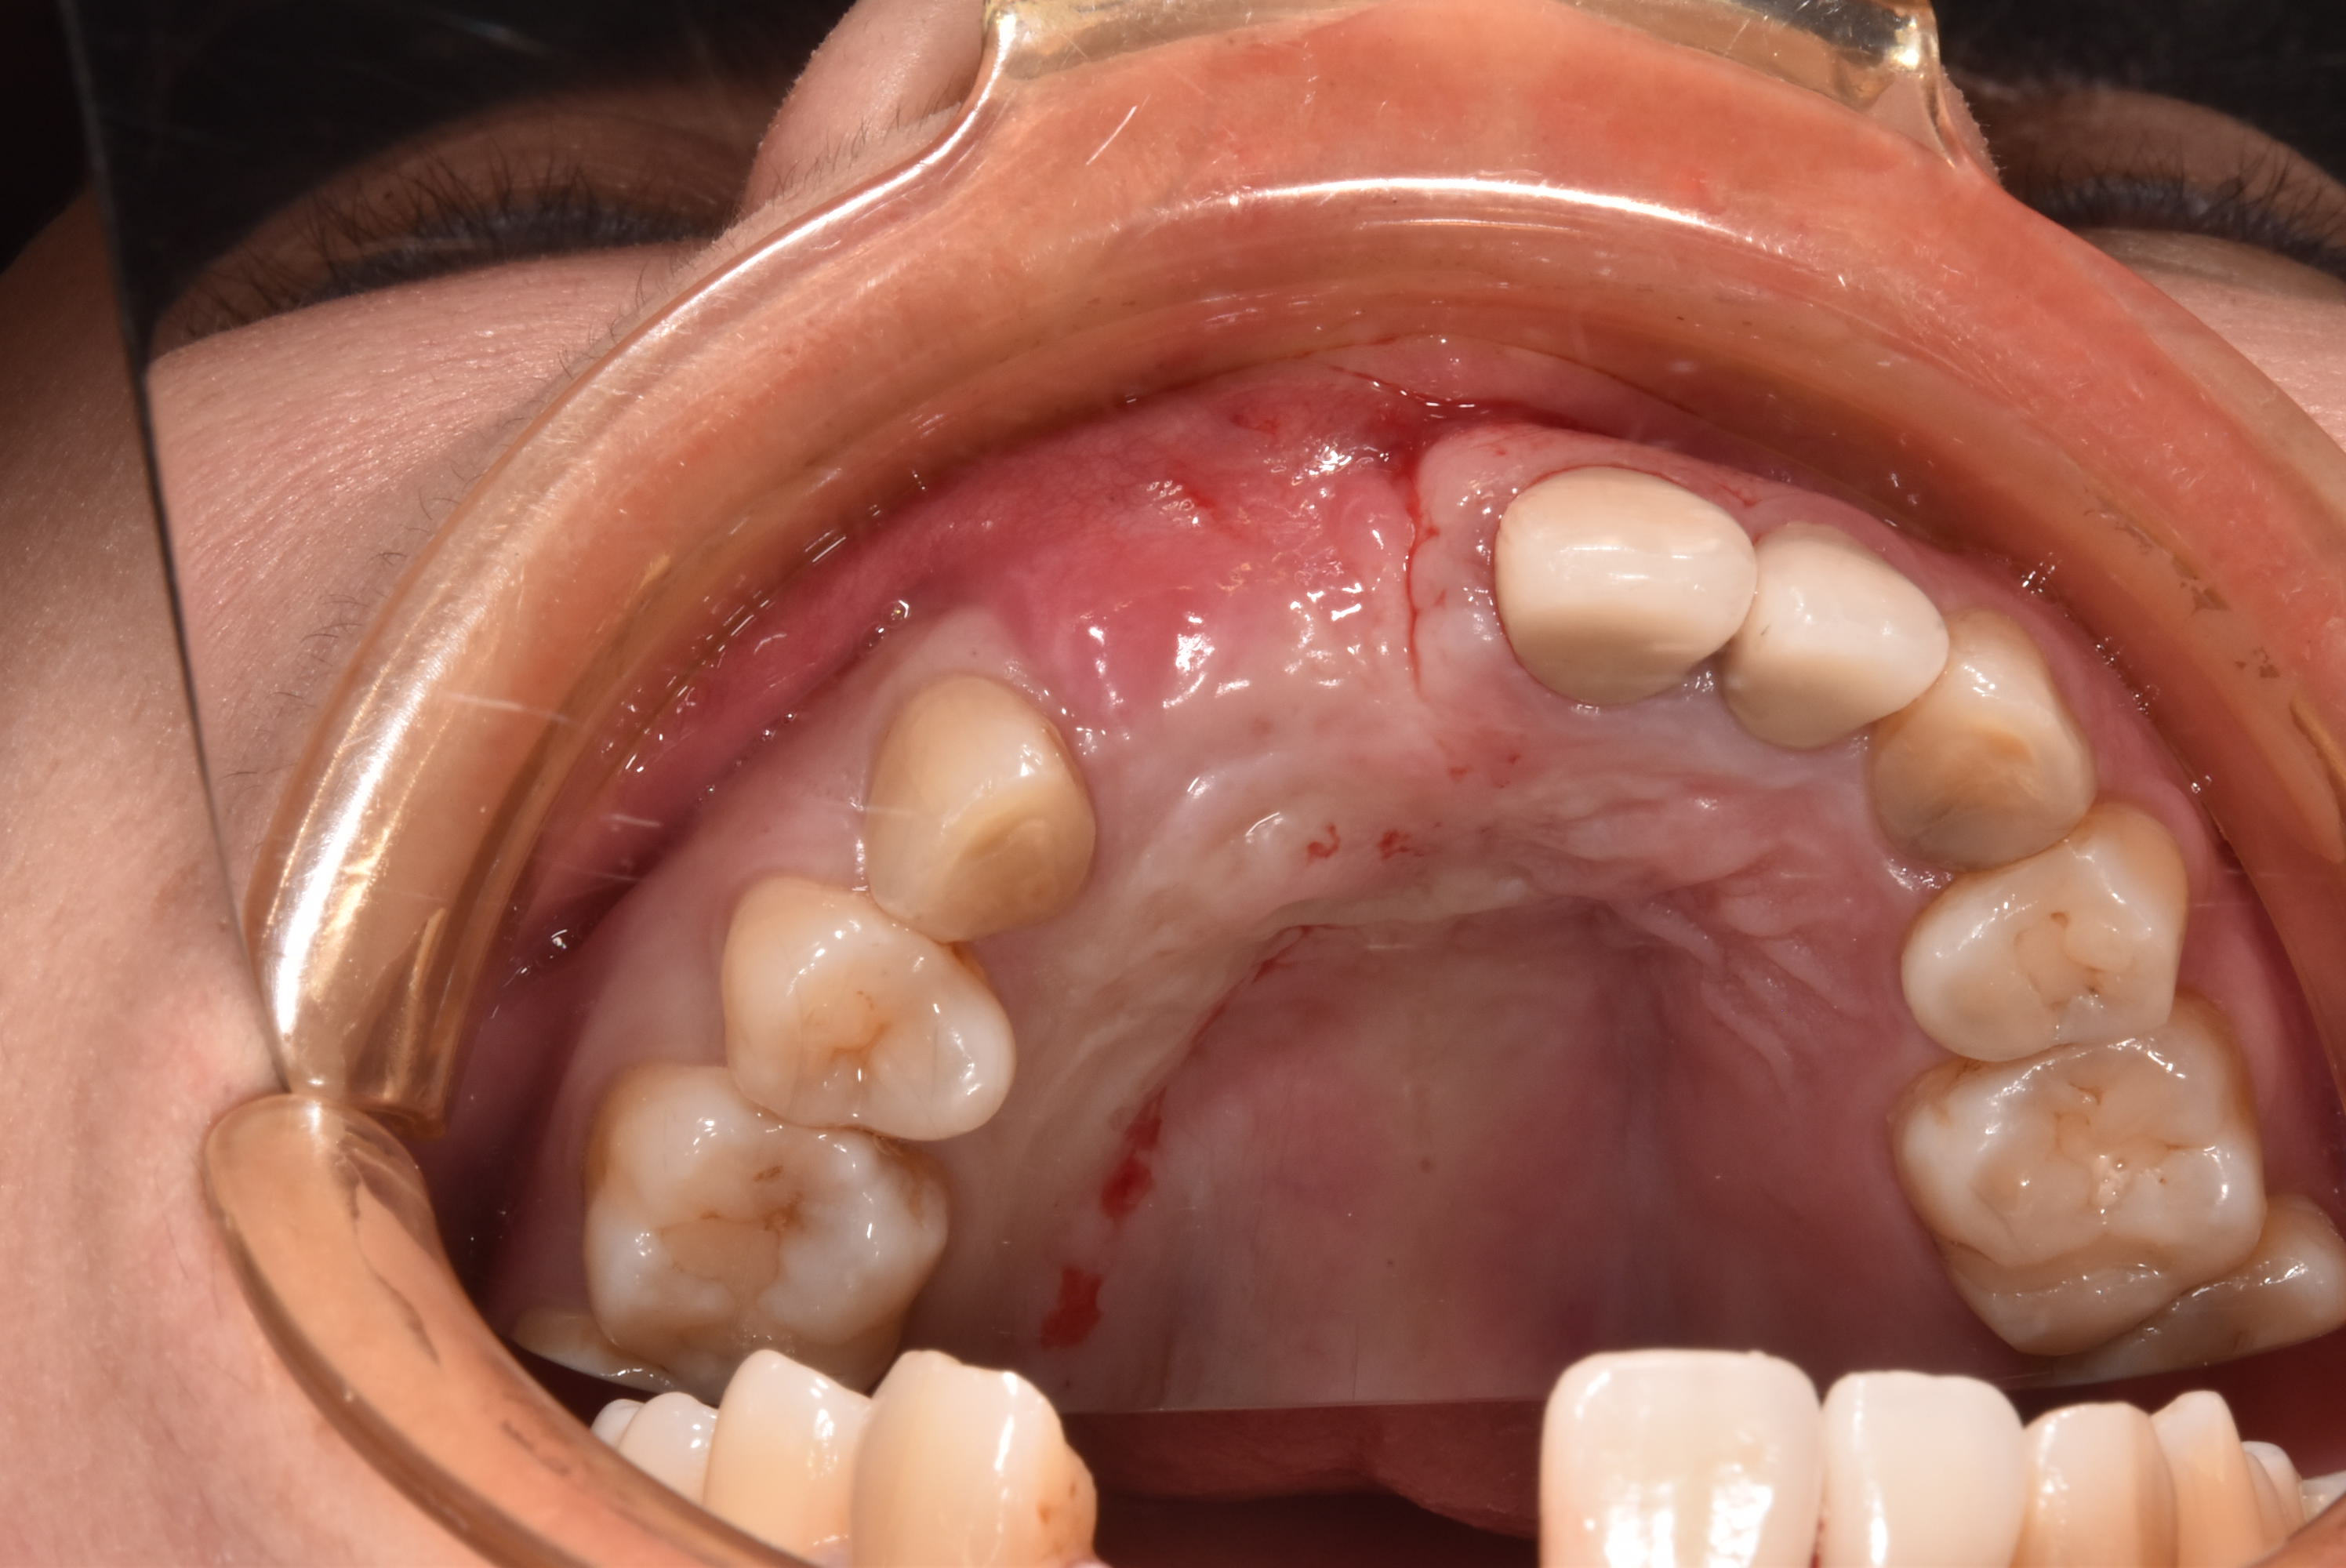

牙齦移植術(補肉)

手術案例

術前加術後案例

案例三